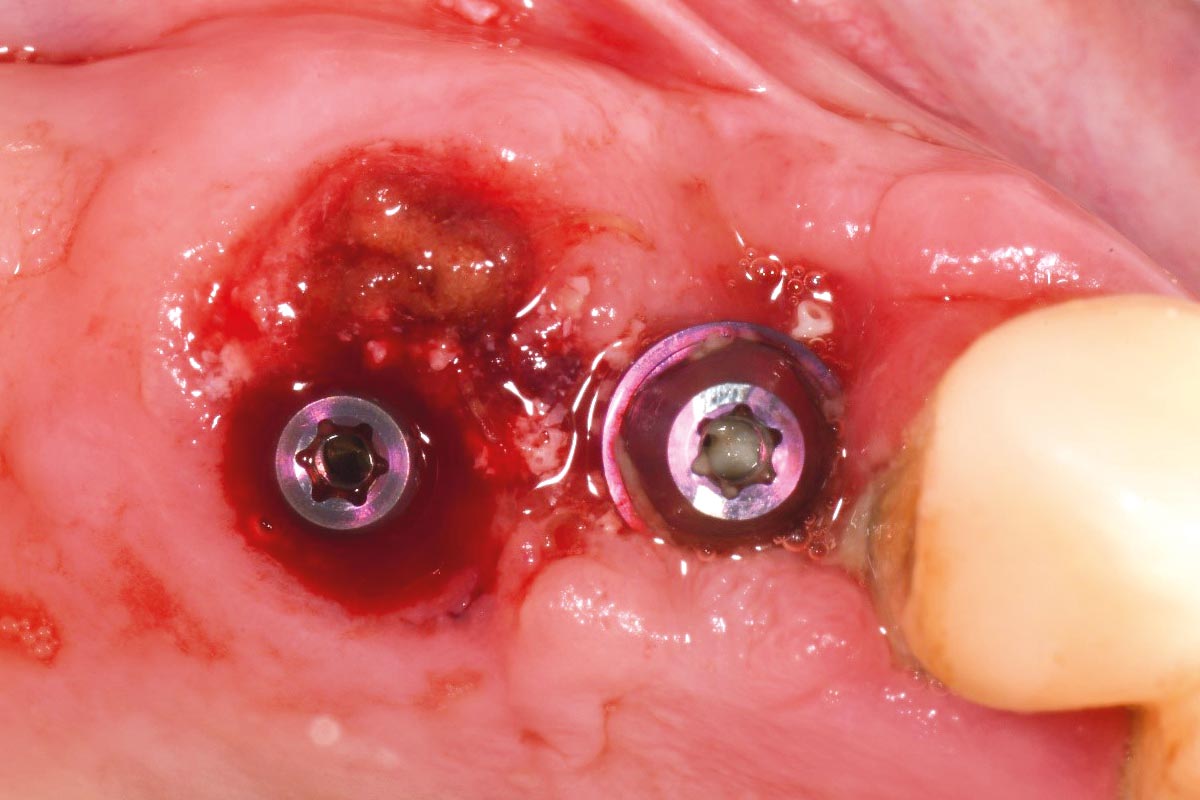

At the six-month re-entry, insufficient regeneration of the buccal plate was observed, compromising the available bone volume for implant placement. To address this deficiency, NOVAMag® SHIELD was introduced to reconstruct the buccal plate. Thus, an implant was placed followed by a membrane placement between the periosteum and the remaining buccal bone without fixation. Additional bone augmentation was performed to facilitate guided bone regeneration.

Three months post-augmentation, substantial bone regeneration and soft tissue integration were observed. The final outcome demonstrated improved aesthetics, function, and implant stability. A final CBCT scan confirmed the success of the procedure, showing sufficient bone volume, density, and proper ridge alignment.